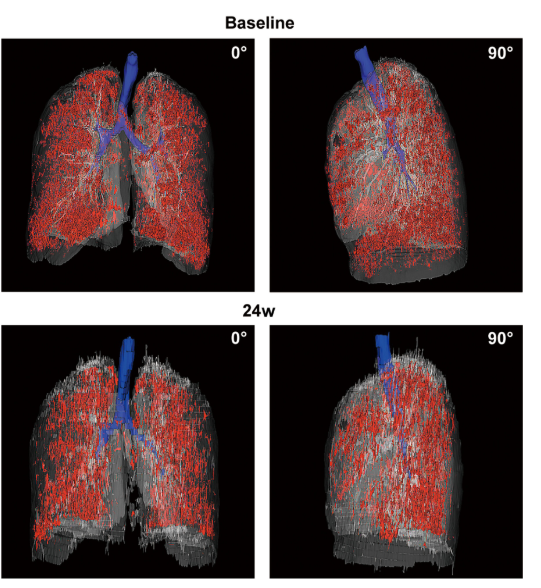

影像學(xué)檢查:對于患者 #2902,定量分析顯示基線時總體肺氣腫面積比為 12.75%,移植后 24 周降至 10.02%。在患者 #8009 中,肺氣腫面積比值從基線的 10.85% 下降到移植后 12 周的 9.08%。CT 圖像的三維可視化顯示,肺氣腫的減輕在下葉比在上葉更明顯。

患者 #2902 自體 P63 細(xì)胞移植前和后 24 周連續(xù)肺部 CT 圖像的三維可視化。

結(jié)論:干細(xì)胞治療24周后,慢阻肺患者的肺功能指標(biāo)、影像學(xué)檢查、生活質(zhì)量和運動功能均得到改善,且未發(fā)生腫瘤或其他嚴(yán)重不良事件。可以達(dá)到干細(xì)胞治療慢阻肺短期療效的結(jié)果。